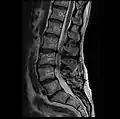

MRI lumbar spine with degeneration, post-hemilaminectomy L4-5 (sagittal T2 FRFSE)